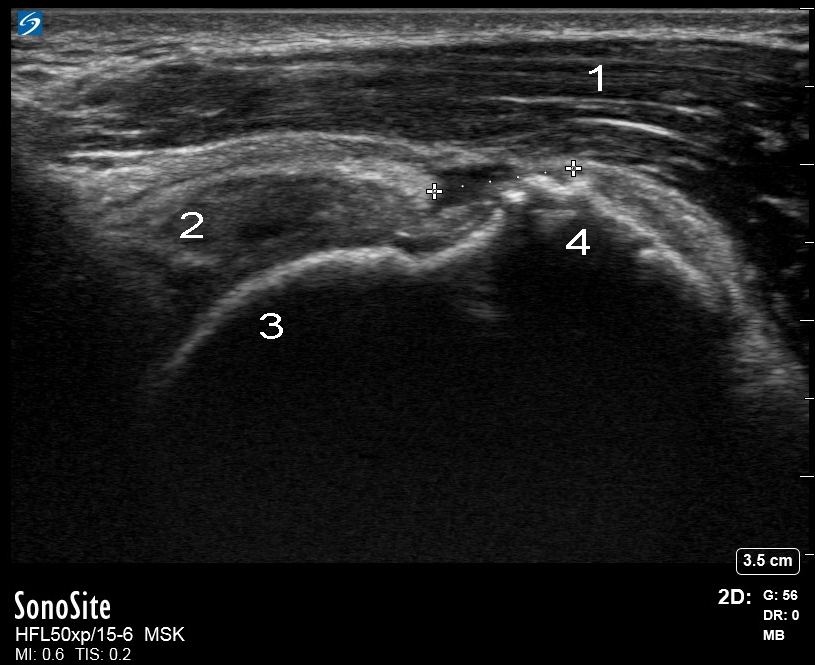

肩部冈上肌腱滑囊表面撕裂图像

左冈上肌纵轴 (LAX)

三角肌

冈上肌

肱骨头

大结节 (GT)